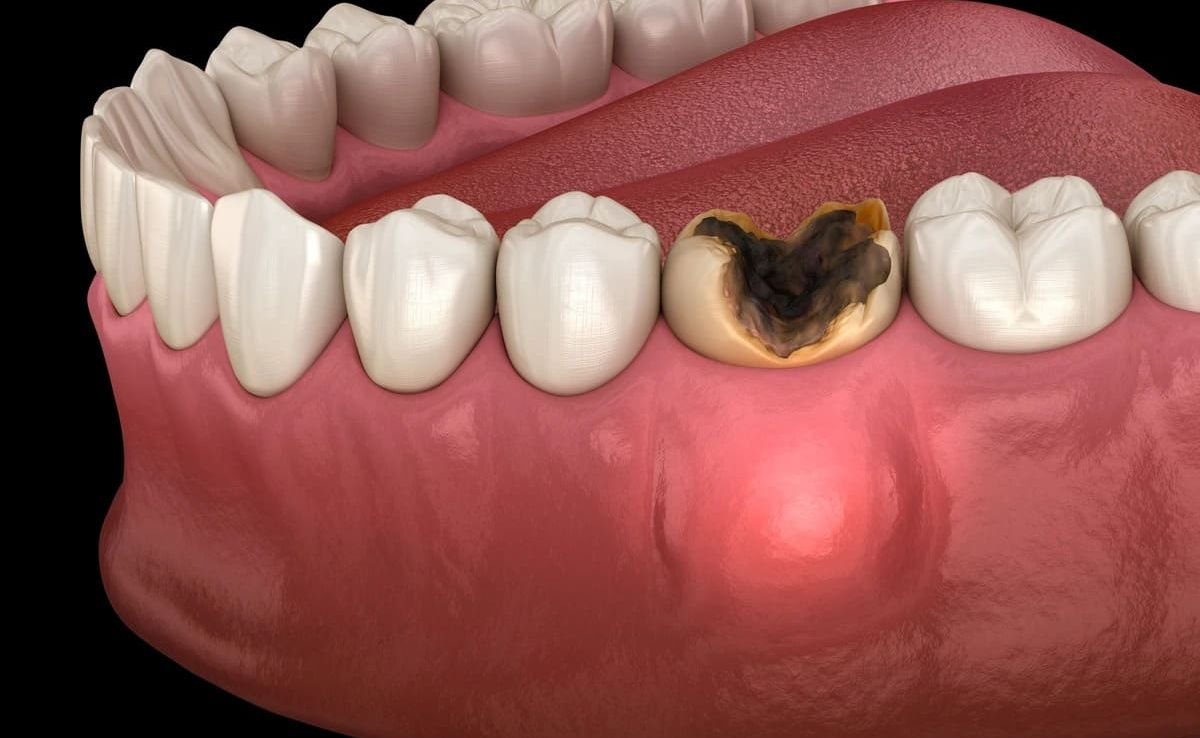

When a tooth is too damaged from decay or trauma to be saved, extraction becomes necessary. We offer both simple and surgical extractions, depending on the position and condition of the tooth.